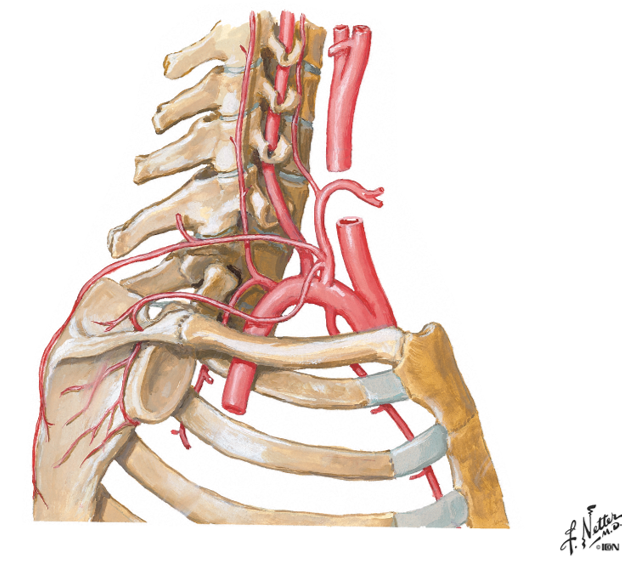

go back and rememeber the subclavian artery and how it had the VA, the thyrocervical trun and the costocervical trunk.....one branch from the costcervical trunk that went up to the skull was the deep cervical artery....what is the branch of this trunk that goes down?

what then branches from the artery?

the supreme intercostal artery

the 1st and 2nd posterior intercostal arteries

notice the subclavian, the costcervical trunk and the deep cervical artery and the supreme intercostal artery...then notice how it splits off into 2 branches under the clavicle

the 3rd through the 11th intercostal arteries branch off from what?

notice it in the picture?

from the aorta